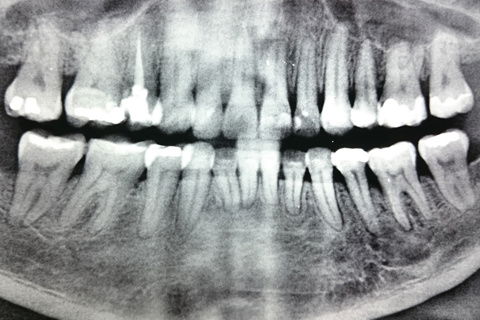

Panorâmica inicial